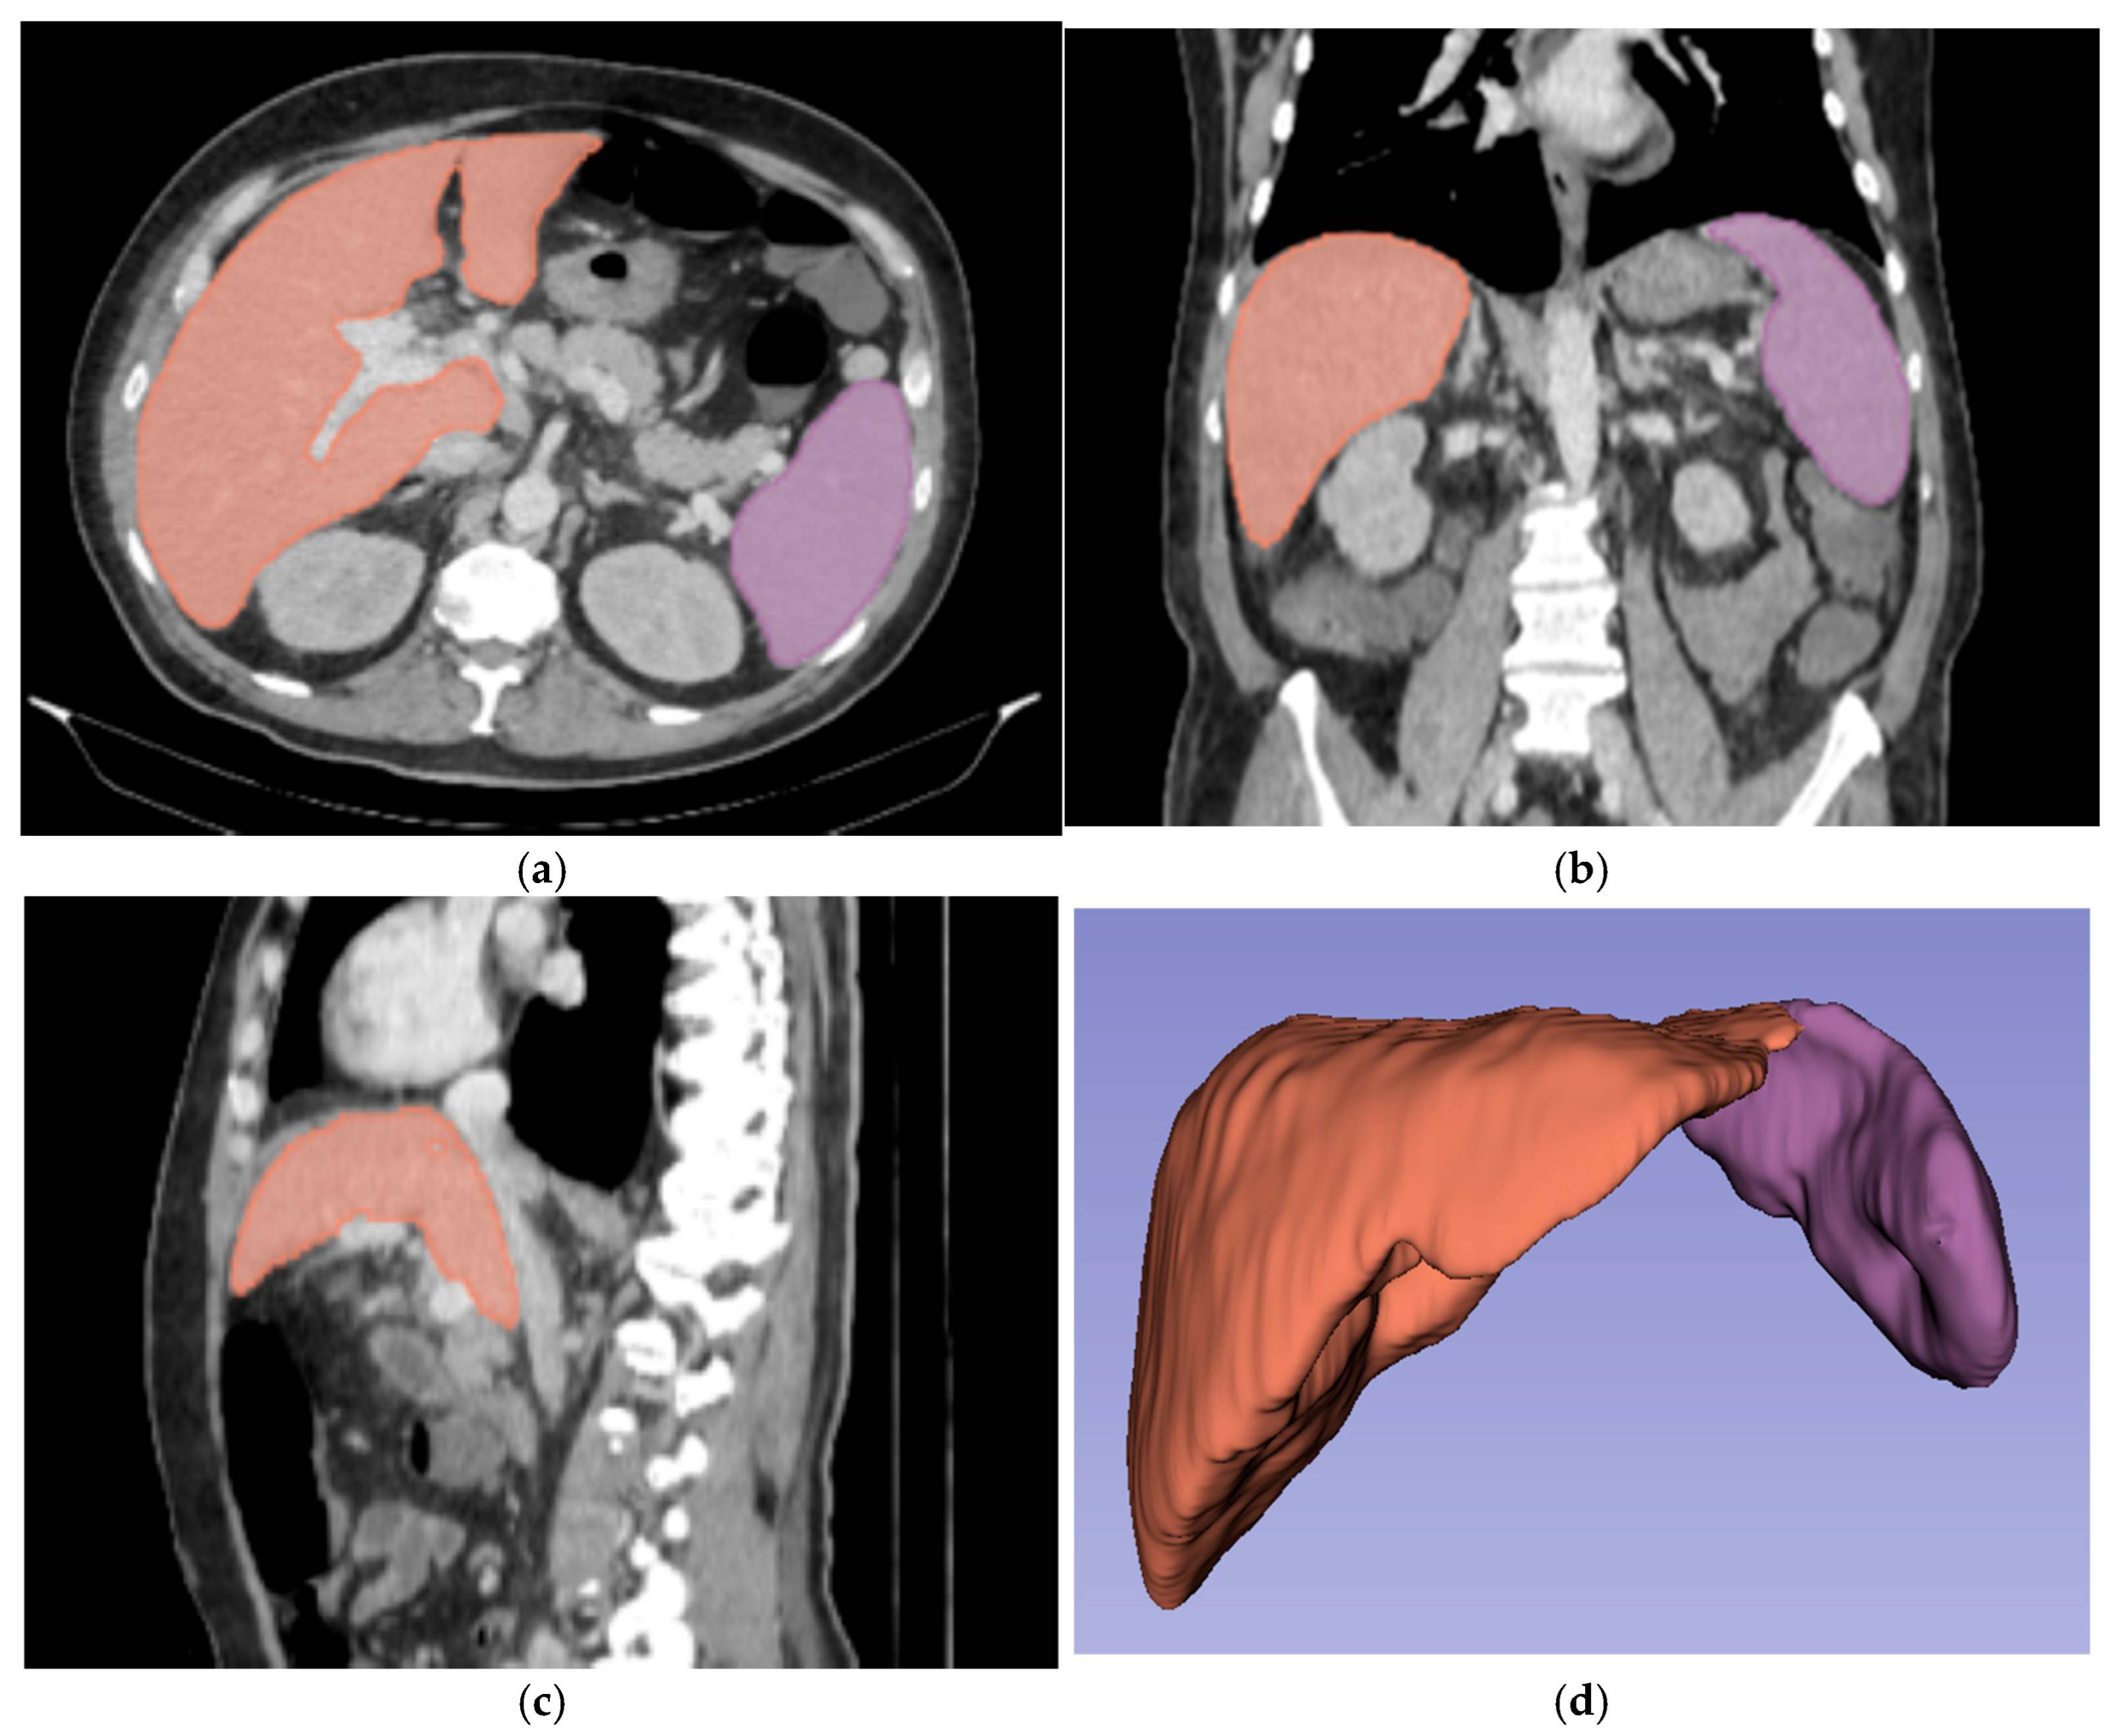

For three-dimensional (3D) segmentation, the TotalSegmentator module in Slicer was used for automated organ segmentation, followed by manual correction of the right and left portal vein, to ensure anatomical accuracy (Figure 2).

Figure 2.

Abdominal portal-venous-phase CT scan: axial, coronal, and sagittal planes (a–c). Example of 3D liver and spleen segmentations. Three-dimensional liver and spleen segmentations were performed by using the TotalSegmentator extension in Slicer software, followed by manual corrections. Images (a–c) show the liver and spleen segmentation in axial, coronal, and sagittal planes. Image (d) shows the final 3D segmentation of these organs.